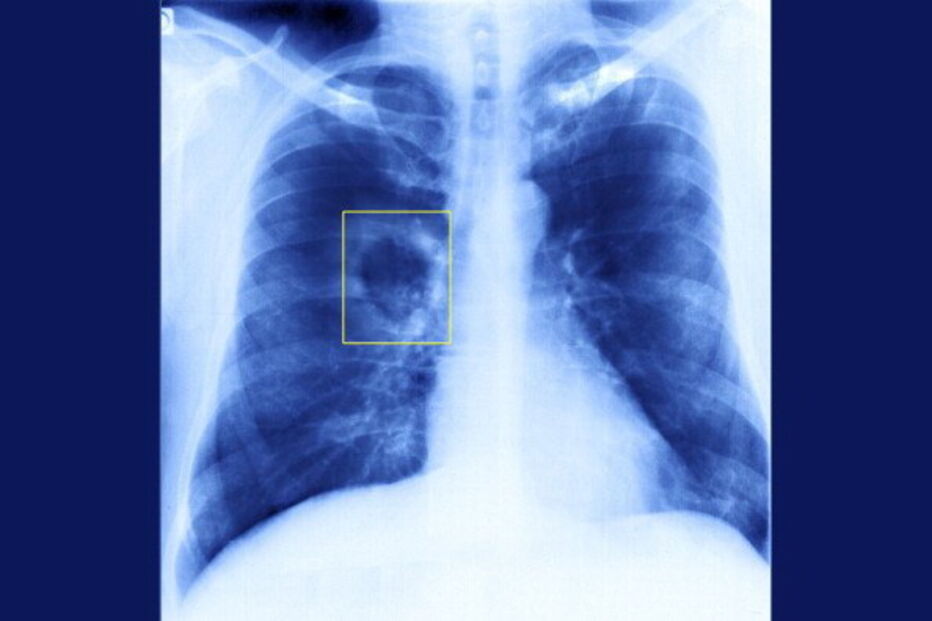

Por isso, salientou, é necessário implementar em todos os agrupamentos de centros de saúde do país "uma rede nacional de espirometria", exame que permite detetar a DPOC e que foi realizado a mais de 3.000 pessoas no âmbito de um projeto-piloto realizado no Algarve e no Alentejo.

"Foi detetada alteração, no sentido de obstrução brônquica, em 26%. E a deteção permite que as pessoas deixem de fumar, façam vacinação da gripe e medicação preventiva, permitindo reduzir as idas às urgências e os internamentos, melhorar a qualidade e a esperança de vida", sublinhou.